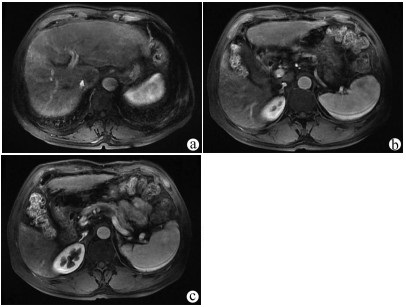

肝病超声诊断指南

中华医学会超声医学分会, 中国研究型医院学会肿瘤介入专业委员会, 国家卫生和健康委员会能力建设和继续教育中心超声医学专家委员会

2021, 37(8): 1770-1785. DOI: 10.3969/j.issn.1001-5256.2021.08.007

超声检查无创、实时、价廉,无辐射、便于反复进行,是最常用的肝脏影像学检查方法。近年来,超声检查新技术如超声造影、弹性成像发展迅速,可有效鉴别肝内占位性病变性质、评估肝纤维化和门静脉高压程度以及监测肝病治疗效果,在临床肝病及其介入治疗中发挥重要诊断价值。本指南规范了肝病多模态超声技术(灰阶超声、彩色多普勒超声、超声造影、弹性超声)检查的仪器调置、患者准备及医生检查方法;对肝脏弥漫性病变(炎性病变、纤维化、硬化)、多种占位性病变及肝病介入操作的多模态超声技术诊断标准进行了定义和规范,同时推荐了超声监测周期及肝脏疾病超声诊断报告书写规范。